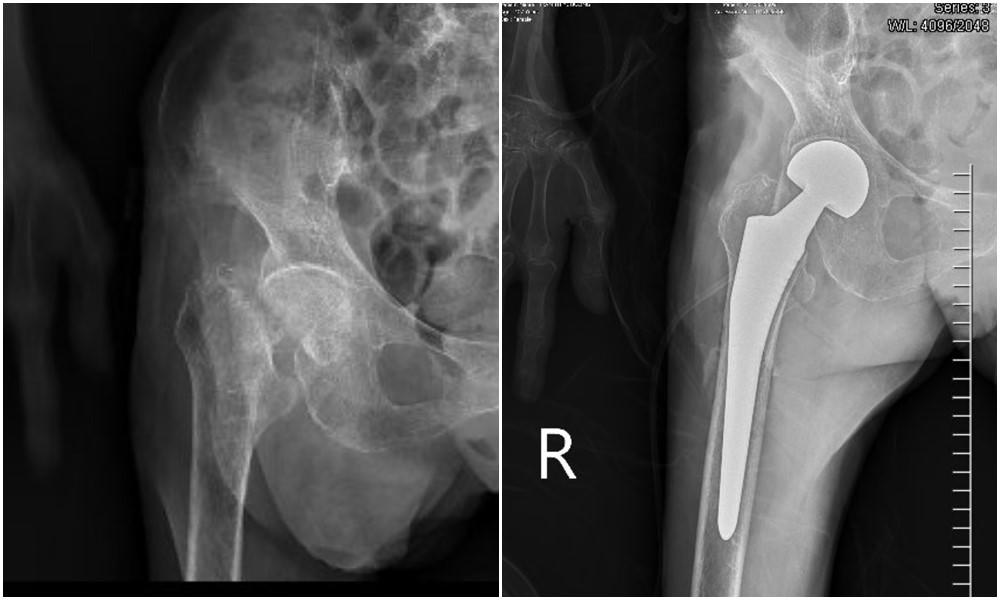

Do cụ tuổi cao sức yếu nên sau khi thăm khám tại y tế cơ sở gia đình quyết định đưa cụ về nhà chăm sóc theo dõi. Tuy nhiên, tình trạng cụ ngày càng nặng nề hơn, đùi phải sưng đau, mất vận động, sinh hoạt phụ thuộc vào con cái. Gia đình đưa cụ đến khám tại Bệnh viện Đa khoa tỉnh Quảng Ninh, qua thăm khám và chụp X-quang, các bác sĩ chẩn đoán cụ C. bị gãy cổ xương đùi phải và được chỉ định mổ thay khớp háng nhân tạo.

Hình ảnh chụp X-quang trước và sau khi thay khớp háng nhân tạo. Ảnh: BVCC |